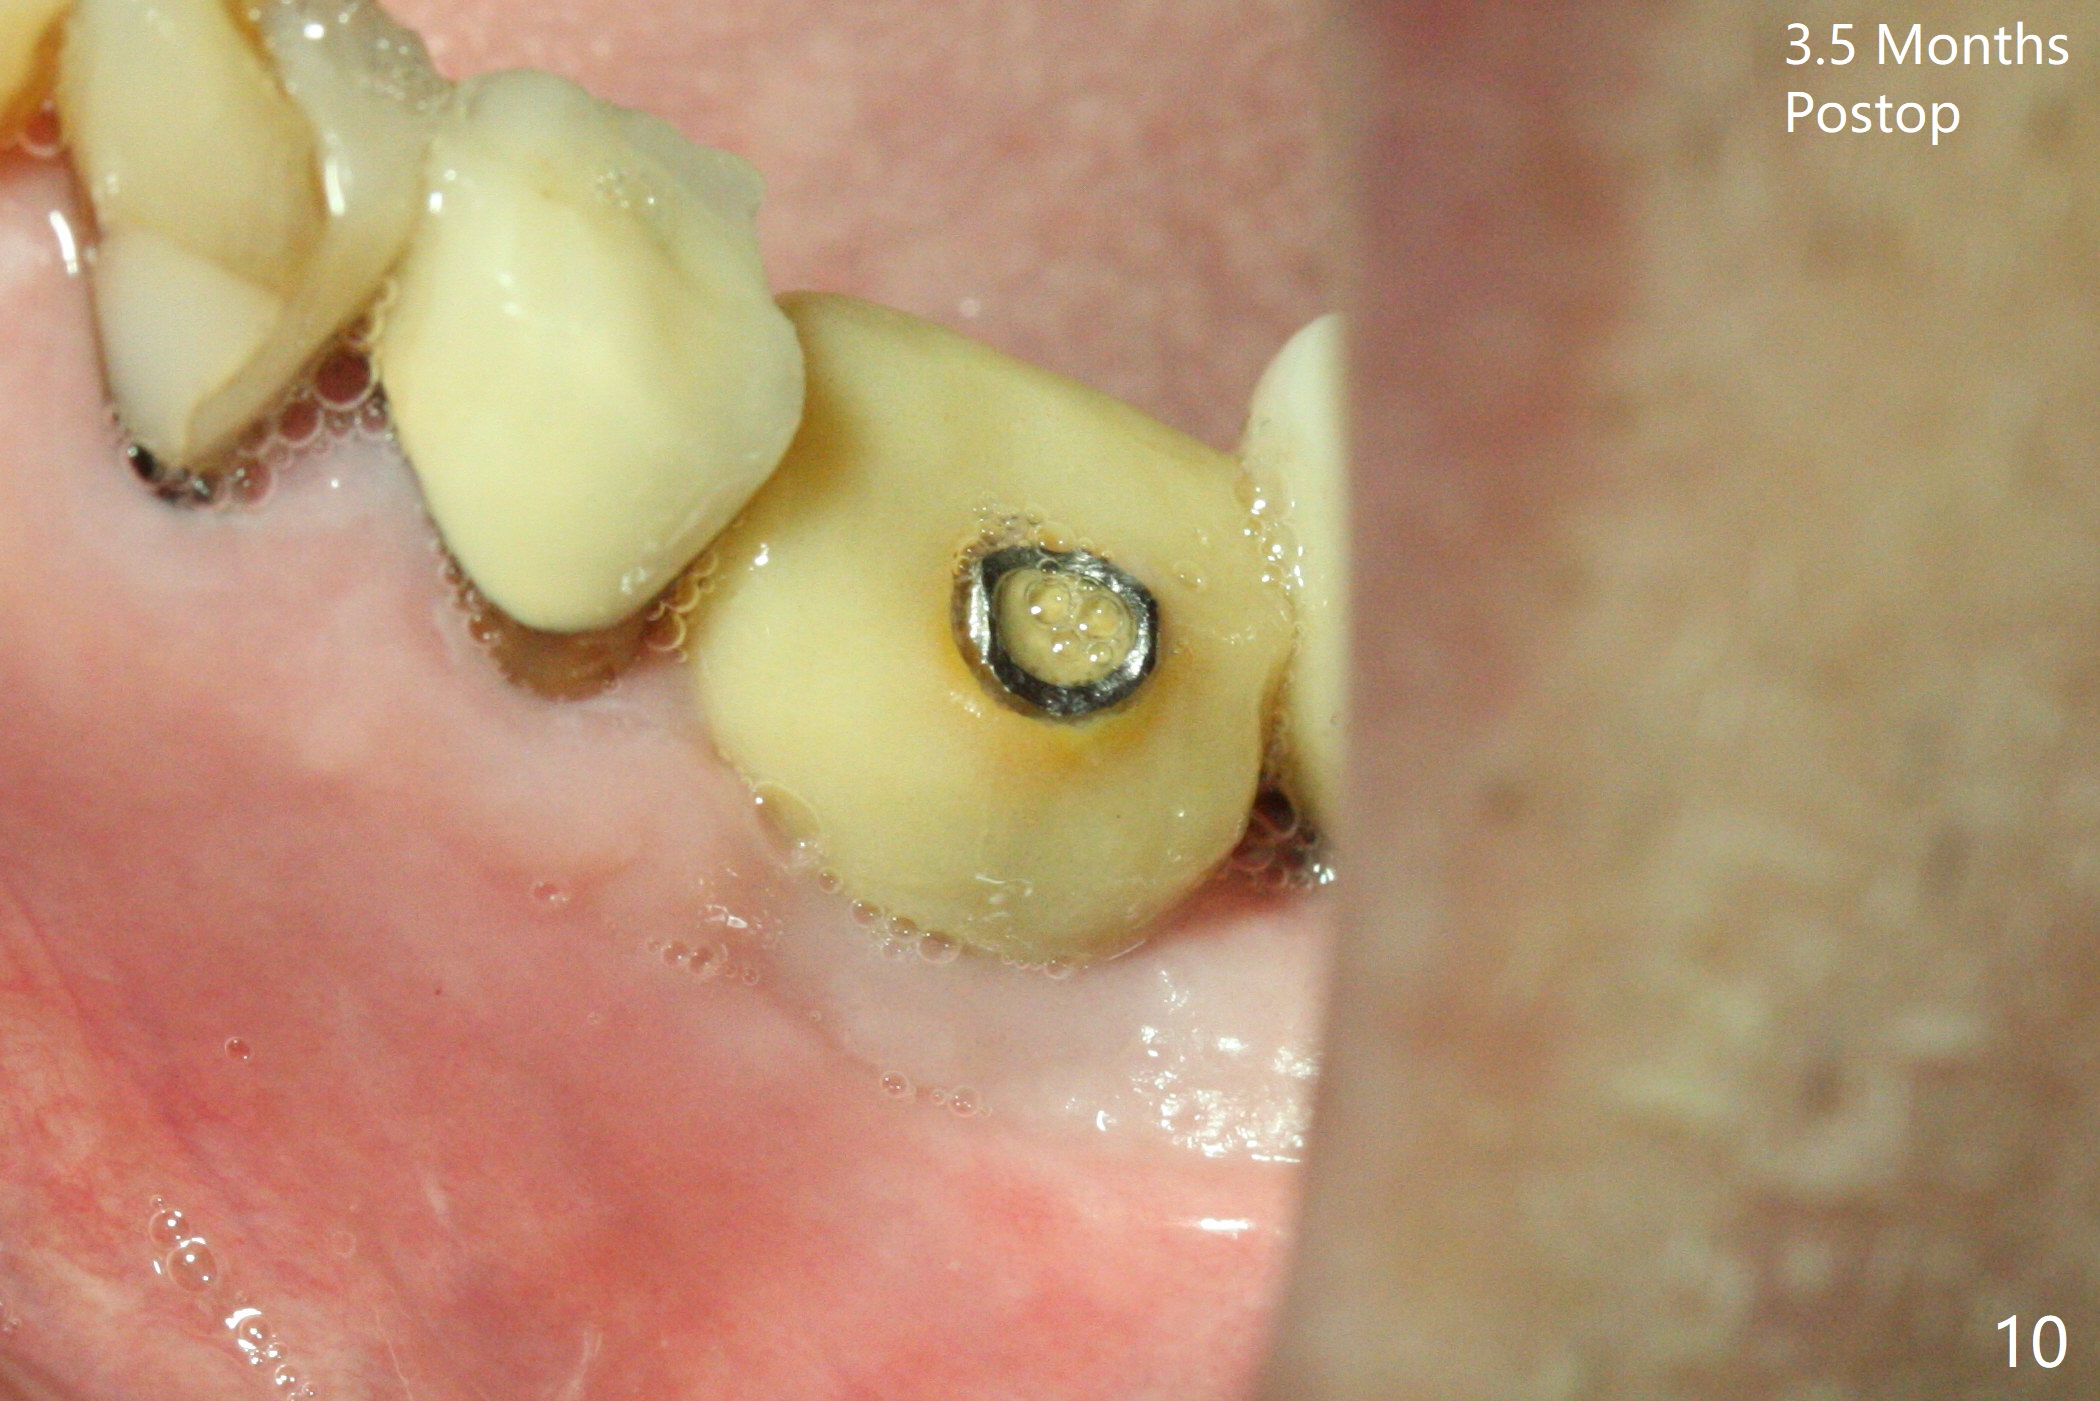

Extraction of the residual roots at #19 (Fig.1) is difficult, partially due to the hard one. The latter contributes to primary stability of 5x10 mm IS implant placed in the septum (Fig.2 (*),3). After change of cementation abutment (5.2x4.5(2) mm (short for provisional)) to hexed temporary abutment (5.2x8(2) mm), Collagen plug and Vera Graft are placed in the remaining mesial and distal socket (Fig.4 *). The last PA is taken when the temporary abutment (Fig.6 (<: hexed portion)) and provisional (P) are removed for modification. Before the abutment/provisional complex returns, a 2nd round of graft is placed (Fig.5 *). After the complex is seated, a 3rd round of graft is placed buccally (Fig.7). The temporary abutment is retightened 2 months postop (Fig.8). The implant appears to be osteointegrated 3.5 months postop (Fig.9). The gingiva looks healthy with (Fig.10) and without the provisional (Fig.11,12). It appears that there is no or minimal buccal plate loss. After insertion of a 5.7 x3 mm 15 degree (B-type) angled abutment (Fig.13) and height adjustment, impression is taken. The provisional is reseated after impression. The mesial bony defect seems to have been repaired nearly 8 months postop, 3 months post cementation (Fig.14 *). The bone density increases mesially 11 months post cementation (Fig.15).